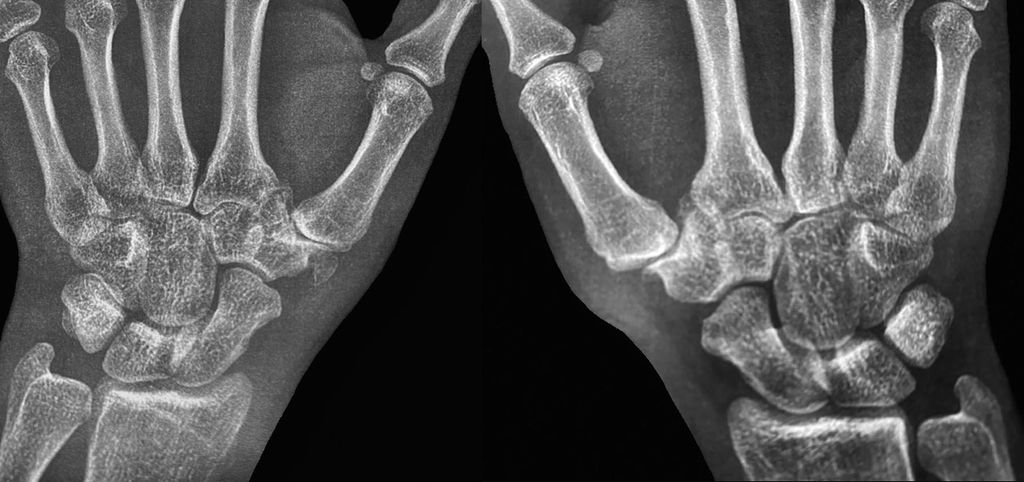

Chronische Instabilitäten, hervorgerufen durch habituelle Bandlaxizität, führen zu einem vermehrten Stress auf ligamentäre Strukturen an der Basis des ersten Metakarpalknochens und zu Gelenksfehlstellungen. Als Folge kommt es zu einer vermehrten Arthrose der betroffenen Gelenke (siehe Abb. 2 und Abb. 3). Diese Veränderungen gehen mit einer erheblichen Morbidität einher und betreffen vor allem postmenopausale Frauen.12 Nach Eaton und Littler wird die Arthrose des Daumensattelgelenkes in 4 Schweregrade eingeteilt.13 Der Schweregrad und die funktionellen Einschränkungen des CMC1-Gelenkes sind mitunter entscheidend bei der chirurgischen Indikationsstellung und machen den Großteil rekonstruktiver Eingriffe aus.5

Abb. 2: Röntgen (Handgelenk a.p.) einer jungen erwachsenen Patientin mit manifester Rhizarthrose und Hypoplasie des Os trapezium beidseits. Der verminderte Gelenksabstand und die veränderte Basis des ersten Metacarpale links sind eindeutig ersichtlich (Eaton-Littler-Grad II). Rechts liegt ein verbreiterter Gelenksspalt entsprechend Grad I vor13

Abb. 3: Röntgenaufnahmen eines erwachsenen Patienten mit manifester Rhizarthrose aufgrund einer beidseitigen Hypoplasie des Trapeziums. Auf der linken Seite ist eine große Ossifikation medial des Trapeziums erkennbar (Eaton-Littler-Grad IV beidseits)13